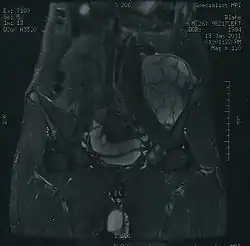

Diagnosis

Imaging studies – including radiographs ("x-rays"), computerized tomography (CT), and magnetic resonance imaging (MRI) – are often used to make a presumptive diagnosis of chondrosarcoma.[9] However, a definitive diagnosis depends on the identification of malignant cancer cells producing cartilage in a biopsy specimen that has been examined by a pathologist. In a few cases, usually of highly anaplastic tumors, immunohistochemistry (IHC) is required.

There are no blood tests currently available to enable an oncologist to render a diagnosis of chondrosarcoma. The most characteristic imaging findings are usually obtained with CT.[10]